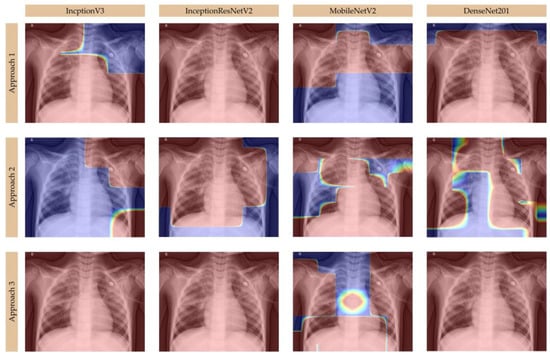

Moreover, we analyzed Grad-CAM visualizations for deep learning models—InceptionV3, InceptionResNetV2, MobileNetV2, and DenseNet201—in classifying healthy lungs, viral pneumonia, and bacterial pneumonia from chest X-ray images, using multiple Grad-CAM approaches to highlight key decision-making areas, as presented in Figure 4, Figure 5, and Figure 6, respectively. In healthy cases, models like InceptionV3 and DenseNet201 show minimal activation, primarily along the ribcage or lung periphery, while viral pneumonia is characterized by diffuse, bilateral activation across both lungs, often including the heart region [,], as seen in MobileNetV2 and DenseNet201, which effectively capture interstitial changes. Bacterial pneumonia, in contrast, is identified by sharp, localized activation, typically within one lung lobe [], with DenseNet201 excelling in its detection due to its highly focused heatmaps, while InceptionResNetV2 also well differentiates the sharply defined activations in specific lobes. Grad-CAM approaches, particularly Approach 3, provide the clearest visualizations, revealing sharp, focused bacterial pneumonia regions and broader, generalized viral patterns, while Approach 1 highlights initial lung field activations, and Approach 2 refines distinctions between pneumonia types. MobileNetV2 performs best for viral pneumonia due to its strong central lung and heart activation, DenseNet201 is the most accurate for bacterial pneumonia, with its distinct lobar focus, and InceptionResNetV2 offers a balanced performance for both. Key takeaways include minimal activation in healthy cases, diffuse patterns in viral pneumonia, and localized, sharp activations in bacterial pneumonia, with DenseNet201 emerging as the most precise model for distinguishing between the two pneumonia types [,]. Overall, Grad-CAM effectively illustrates how these models interpret pneumonia patterns, confirming DenseNet201’s superiority for bacterial pneumonia and MobileNetV2’s strength in viral pneumonia detection.

Figure 5.

Grad-CAM visualizations for viral pneumonia.